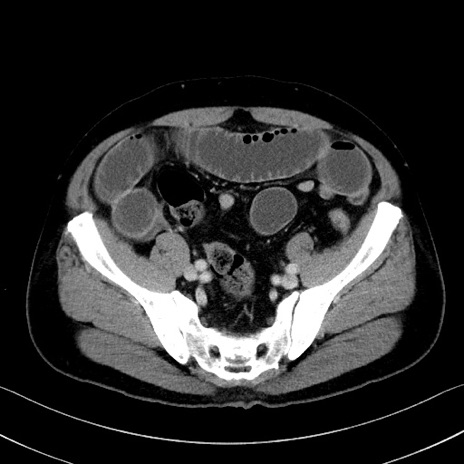

症例35(横断像)

【症例】70歳代 男性

【主訴】腹部膨満、嘔吐

【現病歴】昨日より腹部膨満感出現。本日増悪し、仙痛出現。嘔吐あり、受診。

【既往歴】糖尿病、胆摘後

【身体所見】BP 149/80mmHg、HR 74/min、BT 35.9℃、腹部:膨満、軟、圧痛なし。腸雑音減弱あり。上腹部正中切開瘢痕あり。

【データ】WBC 13500、CRP 1.72